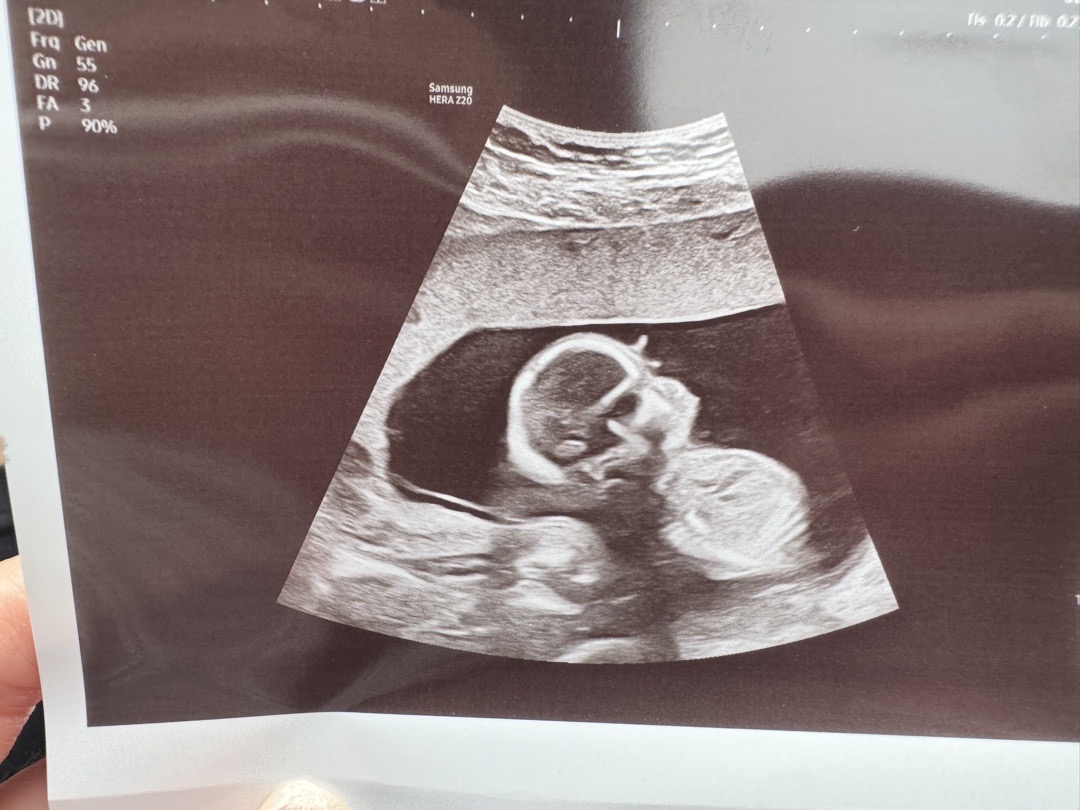

16주차 성별이 애매

성별이 정확히 안나와서요 ㅠ 선생님은 딸인 것 같다는데 다들 어떠신가요. ?

각도법을 볼 수 없는 사진같아요 ㅜ